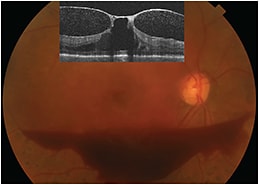

When evaluating these patients, ophthalmologists should use the clinical exam and optical coherence tomography (OCT). It is important to determine if the posterior hyaloid is separated completely (usually signaled by the presence of a Weiss ring) or if there is vitreomacular adhesion (VMA) and/or ERM. In cases where the status of the posterior hyaloid cannot be determined by exam and OCT, B-scan ultrasound may be helpful. Posterior vitreous separation happens in stages; many patients will have perifoveal separation with persistent adhesion at the fovea and disc. One challenge in evaluating patients is differentiating vitreous adhesion from vitreous traction. Focal distortion of the retinal contour at the site of adhesion is more suggestive of traction, as is a more perpendicular angle between the retina and posterior hyaloid (Figure 1). Patients with a flat posterior hyaloid attached to a cyst may be less likely to benefit from vitrectomy (Figure 2).

Figure 1: Fundus photo and OCT (inset) of a patient with proliferative diabetic retinopathy and tractional macular edema. There is focal distortion of the retinal contour around the fovea that is tented up by persistent vitreofoveal adhesion. In addition to causing macular edema, as the posterior hyaloid separated from the macula and optic disc, traction on neovascular tissue has caused subhyaloid hemorrhage which is visible in the photograph and as hyper-reflective points between the retina and posterior hyaloid.